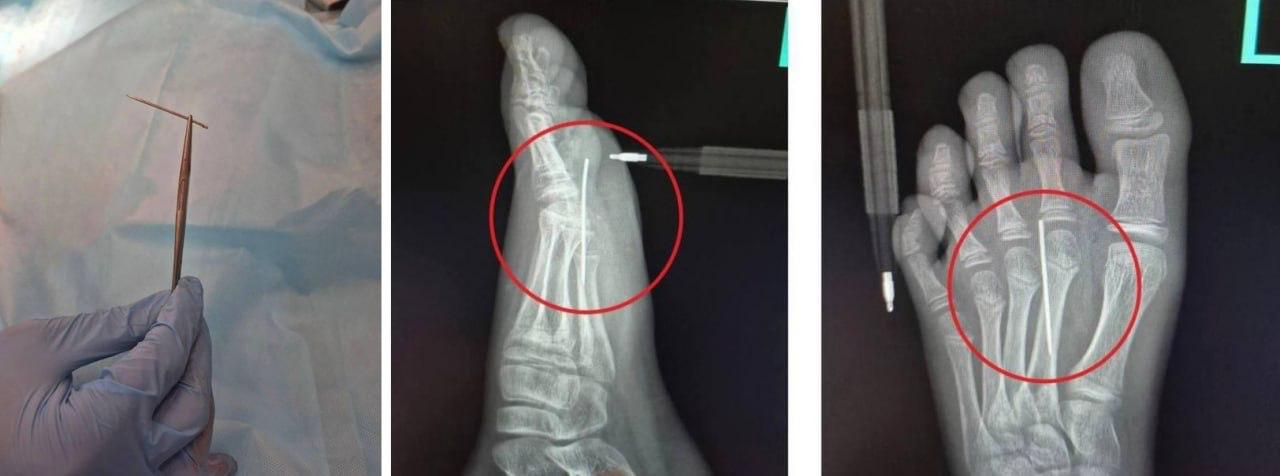

10-летнему школьнику подарили набор с печеньем и металлическими иглами для вырезания фигурок, как в сериале. Но вместо игры он случайно наступил на иглу, и та целиком вошла в ногу. Мальчика увезли в больницу, где врачи вытащили иглу из его стопы.